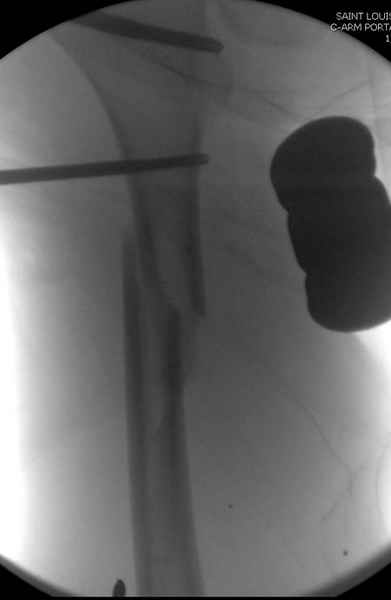

Второй случай тоже репозиция из малого доступа, больному 19 лет, множественные огнестрельные повреждениия конечностей, живота и черепа, правая конечность холодная, без пульсации. Ортопедический диагноз: огнестрельный перелом правого бедра. При срочной ангиографии повреждения сосудов не подтвердилось, конечность из-за ургентности состояния больного зафиксирована временным наружным фиксатором и больной оставлен на операционном столе для срочной лапаротомии хирургической службой.

Больной долго оставался нестабильным, только на 14 день удалось заменить на антеградный интромедуллярный штифт TFN (trochanteric femoral nail) SmithNephew. После неудачной попытки закрытой репозиции, несмотря на использование "joystick", проксимальный стержень от

наружного фиксатора, (перелом начал срастаться) репозицию провели из малого доступа, затем остальные этапы операции.

Случай был представлен из-за того, что больного оперировали после наружной фиксации и был риск инфекцирования через места проведения стержней (на снимках), прошло больше 3 месяцев, выписан из амбулаторной службы из-за отсутсвия надобности дальнейшего наблюдения.